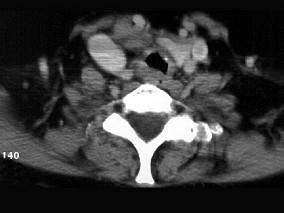

问题 男性,50岁,声音嘶哑近一年,近来感呼吸困难,CT扫描如图所示,请选择正确的描述和结论 ( )

选项 A、考虑为喉气管淀粉样变性 B、考虑气管结核 C、气管后方见软组织肿块 D、肿块内可见致密钙化影 E、喉、气管壁增厚

答案 ACDE